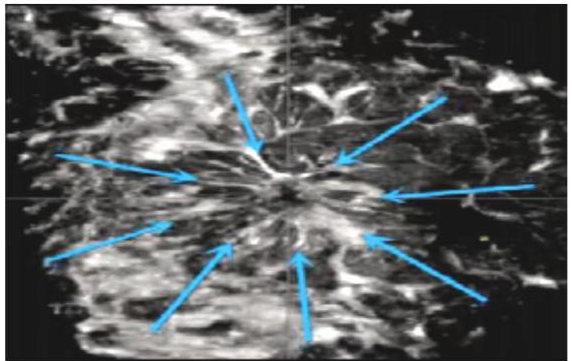

根据2022年版专家共识,自动乳腺容积超声成像对乳腺病灶的评估和HHUS一致,参考BI-RADS分类词典内容,此外它增加了冠状面图像信息,有些特殊特征如下:汇聚征、跳跃征、肿块周边的高回声环和低回声环、白墙征象等,这些特征性征象描述对肿块性质鉴别诊断有助于判断,从而进一步提高了乳腺恶性肿瘤的早期检出率。ABVS 能提高超声对微钙化的检出率,特别是无肿块背景下的微钙化,ABVS 的冠状面成像能直观显示微钙化分布范围,提高超声对导管内癌的鉴别诊断能力。

汇聚征:低回声肿块周边呈现向中心汇聚的放射状排列高回声。